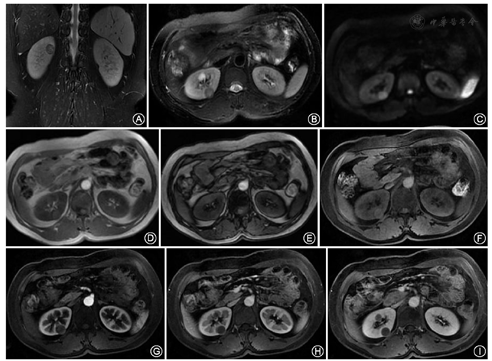

T2WI:31例肿瘤实性成分以等低信号为主(图1A,图1B),3例肿瘤实性成分呈不均匀稍高信号;33例(97.1%)肿瘤出现假包膜。T1WI:29例肿瘤以稍低或等信号为主,5例呈均匀高信号(图1D, 图1E, 图1F, 图1G, 图1H, 图1I);12例(35.3%)肿瘤可见斑片状高信号,提示出血。与正相位图像比较,反相位图像4例(11.8%)肿瘤信号局部减低,提示含脂质成分。22例(64.7%)肿瘤发生囊变;9例(26.5%)肿瘤可见不规则坏死区。DWI:10例(29.4%)肿瘤呈等低信号;24例肿瘤呈高信号为主(占70.6%),其中8例呈环形高信号,12例局部呈结节样高信号,4例肿瘤呈均匀高信号(图1C)。